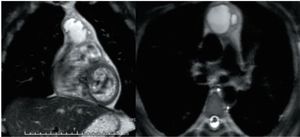

A 39-year-old man is diagnosed with pure post-pubertal teratoma of the testis. What are the best steps of management?